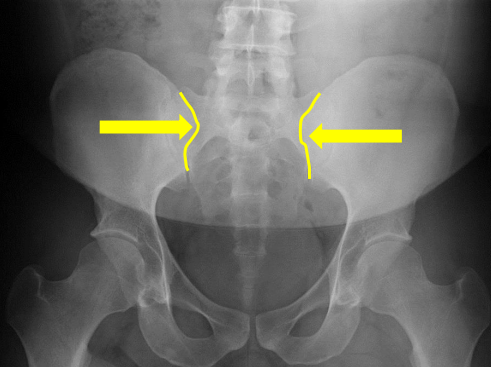

Sacral groove

Lateral aspect of sacrum

Medial aspect of ilium